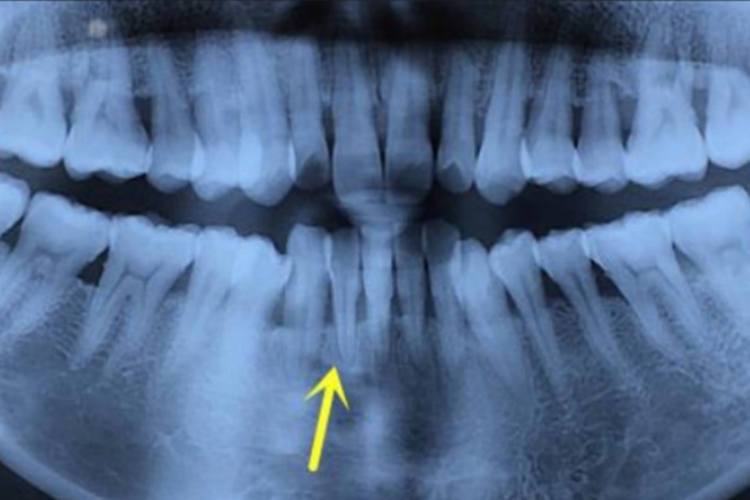

固有牙槽骨是牙槽窝的内壁,又称筛状板,围绕于牙根周围,与牙周膜相邻。固有牙槽骨骨质致密,可将其看作一种特殊的骨密质,其靠近牙周膜的表面由含有孔隙的平行骨板组成,骨板的排列方向与牙槽骨内壁平行。它在X线片上呈围绕牙根的连续阻射白线,又称硬骨板。

持续性根尖周炎症可导致根尖周硬骨板的吸收,在X线片上可表现为阻射白线的模糊、中断,甚至消失。硬骨板矿物质被吸收30%-50%时,在X线片上才能显示出来。因此,早期根尖周病损不一定能被X线片检出。